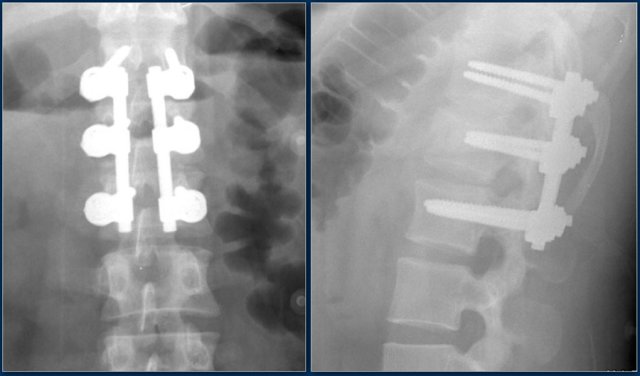

This is an interesting case since non-surgical management was initially attempted in this patient.

However when we classify according to the TLICS-score, we give 4 points for the morphology and 3 points for the PLC.

Assuming the neurological exam was normal, this patient would still get 7 points.

Unfortunately, but not unexpectedly, conservative management failed with near-dislocation.

Finally a posterior spondylodesis was performed.